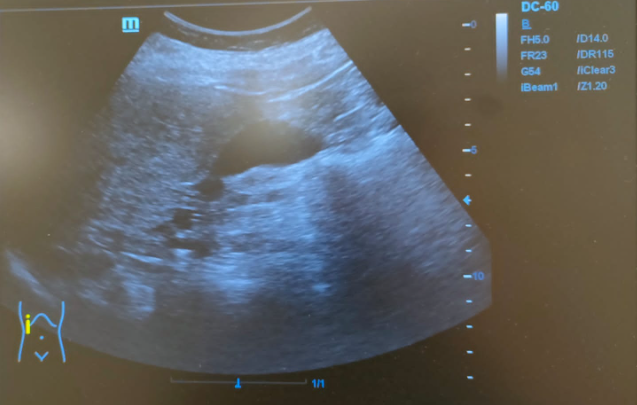

Hallazgos ecográficos

Hígado de tamaño normal, contornos ligeramente nodulares, alteración de la ecoestructura compatible con hepatopatía crónica. Nódulo hipoecoico de contornos irregulares en lóbulo hepático izquierdo de 16x24mm sin captación Doppler.